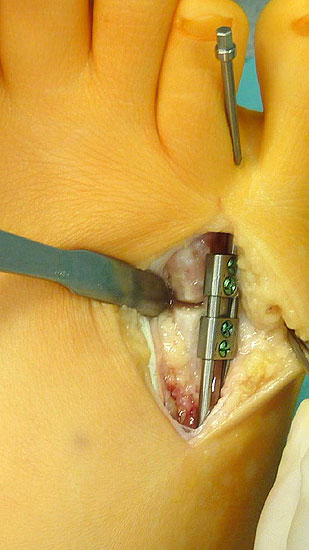

Das im Folgenden vorgestellte Operationsverfahren beschreibt die Kallusdistraktion von Metatarsalia nach den Prinzipien von Ilisarov 21 unter Verwendung eines internen, winkelstabilen Titan-Minifixateur (Klauser 2009). Der interne Distraktor ermöglicht während der Distraktions- und der Durchbauungsphase aufgrund seiner hohen Stabilität je nach Modell (18 mm, 23 mm) eine Verlängerung von bis zu 25 mm. Nach interner Anlage des Minifixateurs, meist lateral, kann über eine kontinuierliche Kallusdistraktion der Metatarsalebogen unter frühzeitiger Mobilisation im Gips oder Short-Walker rekonstruiert werden 15. Über einen interdigital und transcutan ausgeleiteten Aktivatorstab wird die Distraktion vom Patienten selber täglich morgens und abends durchgeführt. Zusätzlich vorliegende Strahlpathologien, wie zum Beispiel eine verkürzte Strecksehne oder ein kontraktes Metatarsophalangealgelenk können im Rahmen der Erstoperation ebenso therapiert werden wie z.B. ein Hallux valgus, ein Hallux valgus interphalangeus und/oder ein Digitus quintus varus (Klauser 2009). Nach Rekonstruktion des Metatarsalebogens wird in einem zweiten, kleinen Eingriff der Aktivatorstab über eine Spezialpinzette diskonnektiert und entfernt, wobei der Distraktor als interne Fixation belassen wird. Die Entfernung des Distraktors erfolgt in der Regel nach 9 – 12 Monaten, da es sich meist um angeborene kindliche Fehlbildungen handelt (Brachymetatarsie) und eine operative Intervention frühzeitig im Kindesalter erfolgen sollte (Klauser 2009).

• Laterale Implantation des Distraktors und damit besseres Anmodellieren entsprechend der ovalen Knochenstruktur des Os metatarsale und somit - sowie aufgrund der geringen Aufbauhöhe des Minifixateur - gute Weichteildeckung (Klauser 2009).

• Zweiter Eingriff: Diskonnektieren des transcutan ausgeleiteten Aktivator, falls möglich, über eine kleine Inzision von 1,5 bis 2 cm, in der Regel jedoch über Eröffnen der alten Schnittführung mit ggf. Strecksehnenverlängerung und erneutem Grundgelenk-Release sowie ggf. Ausleiten einer Penroselasche oder einer Gentamycin-Palacos-Minikette.

• Spezial-Pinzette zur Abkoppelung des Aktivators (Zweiteingriff) (siehe auch Abb. 8).